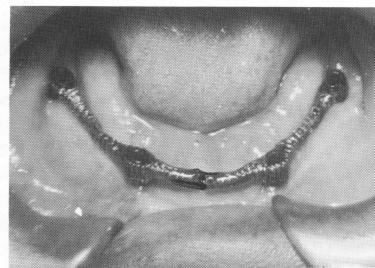

After about 3 to 6 weeks, the implant should have completely set and the surrounding tissues should be sufficiently healed to take the final "pick-up" impression for the final implant prosthesis (Fig. 12-32) . The superstructure framework is first placed over the four implant abutments (Fig. 12-33), and an accurate wax or stone occlusal record of centric relation is taken and the vertical dimension established (Fig. 12-34) . The superstructure is then picked up with one of the elastic impression materials (Fig. 12-35) or with one of the alginate materials (Fig. 12-36). All the soft tissue underneath the superstructure should be included in this impression. Instead of processing the denture, a wax-up of acrylic teeth fitted to the metallic superstructure should be tried during the next visit so that the bite, articulation, vertical dimension, and balancing of the case can be corrected (Fig. 12-37). Finally, the com-

Fig. 12-34. A wax interocclusal record of centric relation is taken.

Fig. 12-35. The superstructure framework is then "picked up" with an elastic impression.

Fig. 12-36. Sometimes an alginate impression is used to "pick up" the superstructure.